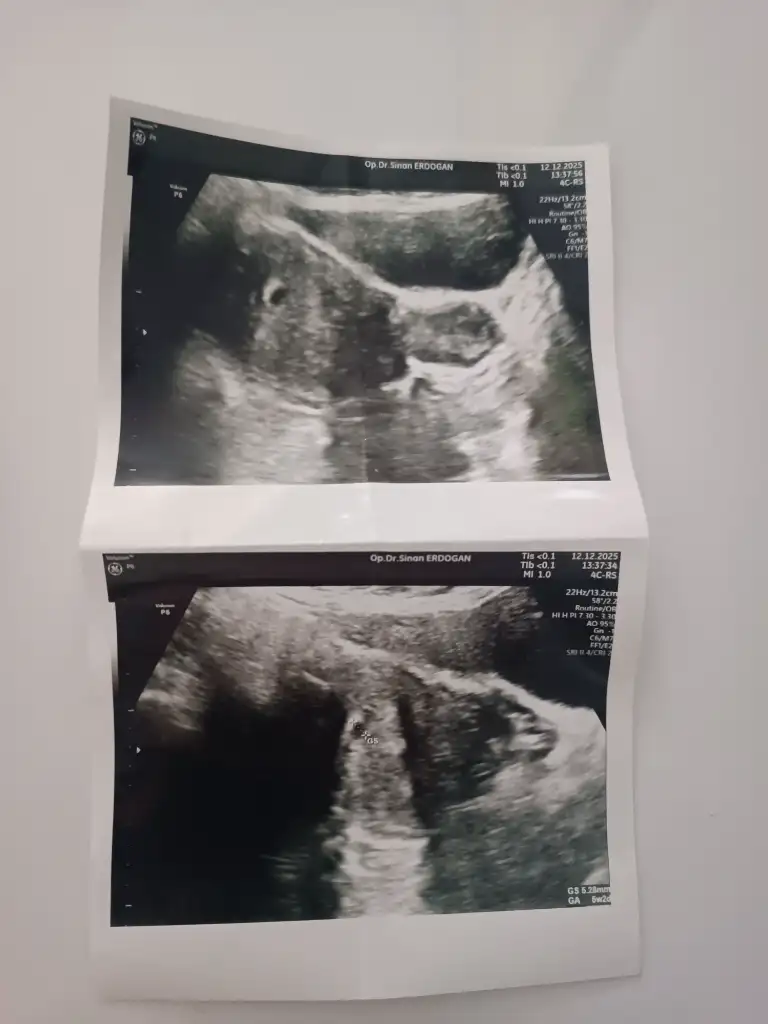

5+4 sat ile uyumlu. Doktor da 5+4 dedi. Bazen farklı alan ölçümlerinde değişebilirmiş.Merhaba sizinki 5+4 mü 6+4 mü

Benimkide byleydi 5 haftalık benim rahmimde tesrs arkaya dönük oyuzden karından ultrason ile çok zor gördü yani şimdi senin haftan hangisi olyor benim son adet tarihine göre şuan 6 hafta olduTabi

5w4 yazan kısım haftası, sağ al köşede de 6w4 yazıyor. Kese 143 gibi bilgiler var

Bende dün gittim ve minik bir kese gördük karından ama pazartesi tekrar gideceğim kese içinKeseyi 4+6da vajinal muayene ile gördük. Şimdi kalp atışı için heyecanla bekliyorum.

Canın son adet tarihine göre 7 hafta şuanVajinal olduğu için olabilir belki ozman benim karından ultrasondu haftaya gideceğim ama bnce senin haftan 5+4degildir